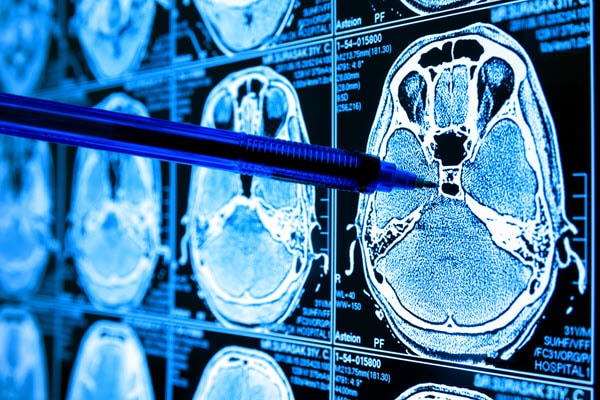

(Source: zapp2photo - stock.adobe.com)

Scientists have used many ways of testing and looking at cancer over the years, but microscopy and other imaging techniques have been some of the key methods. The days are gone when a scientist would look under the microscope and come to a conclusion without any computer assistance. In recent years, a number of computer software programs enabled scientists to look at the shape, size, and morphology of imaging samples, including cells. However, many of these programs still require human input to characterize where the points of interest, in this case, the cancer cells, start and where they stop. These imaging methods have been designed for a range of analysis equipment, from the simple lab bench microscope to MRI scanners.

So, while there are effective methods for cancer diagnosis—which is why humans as a whole have gotten better at recognizing and understanding the disease—most of these methods are still prone to human error. Even a small error can cause a misdiagnosis. Machine learning emerged in the last few years as a potential solution to this. Results, to date, have shown the ability to analyze imaging samples and pinpoint the presence of cancer cells with a high degree of accuracy.